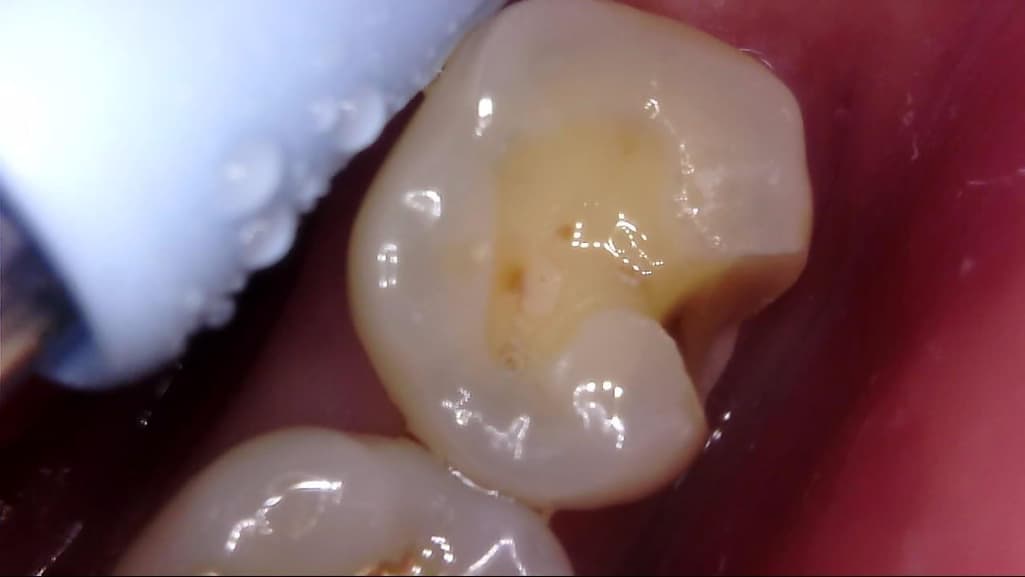

이차 우식이 상당히 깊게 발생하였는데, 치료 과정에서는 아래 사진과 같이 선생님께서 아래와 같이 일부 갈색 부분을 남긴 채 치아 삭제를 마치고 보철을 진행해 주셨습니다.

선생님께서는 "해당 부분은 착색 부위로, 이대로 덮어도 무방하다"라고 말씀 주셨고, 저 역시 더 이상 파고들어가면 신경치료가 예상되어 최선의 치료를 해 주셨다고 생각합니다.

사진에 보이는건 일단 착색과 2차 충치가 섞여 잇는거 같습니다. 충치를 제거하는 저스피드 기구로 제거를 해보기너 눌러 봐서 단단하면 충치가 아닙니다.

사진으로 보이는 부분은 충치에 어느정도 영향을 받은 부위는 맞습니다. 하지만 감염이 되어 있는것으로 보이지는 않습니다.

착색은 아니고 이환 상아질 남긴 것 같습니다 감염 상아질은 깔끔하게 다 제거 됐습니다